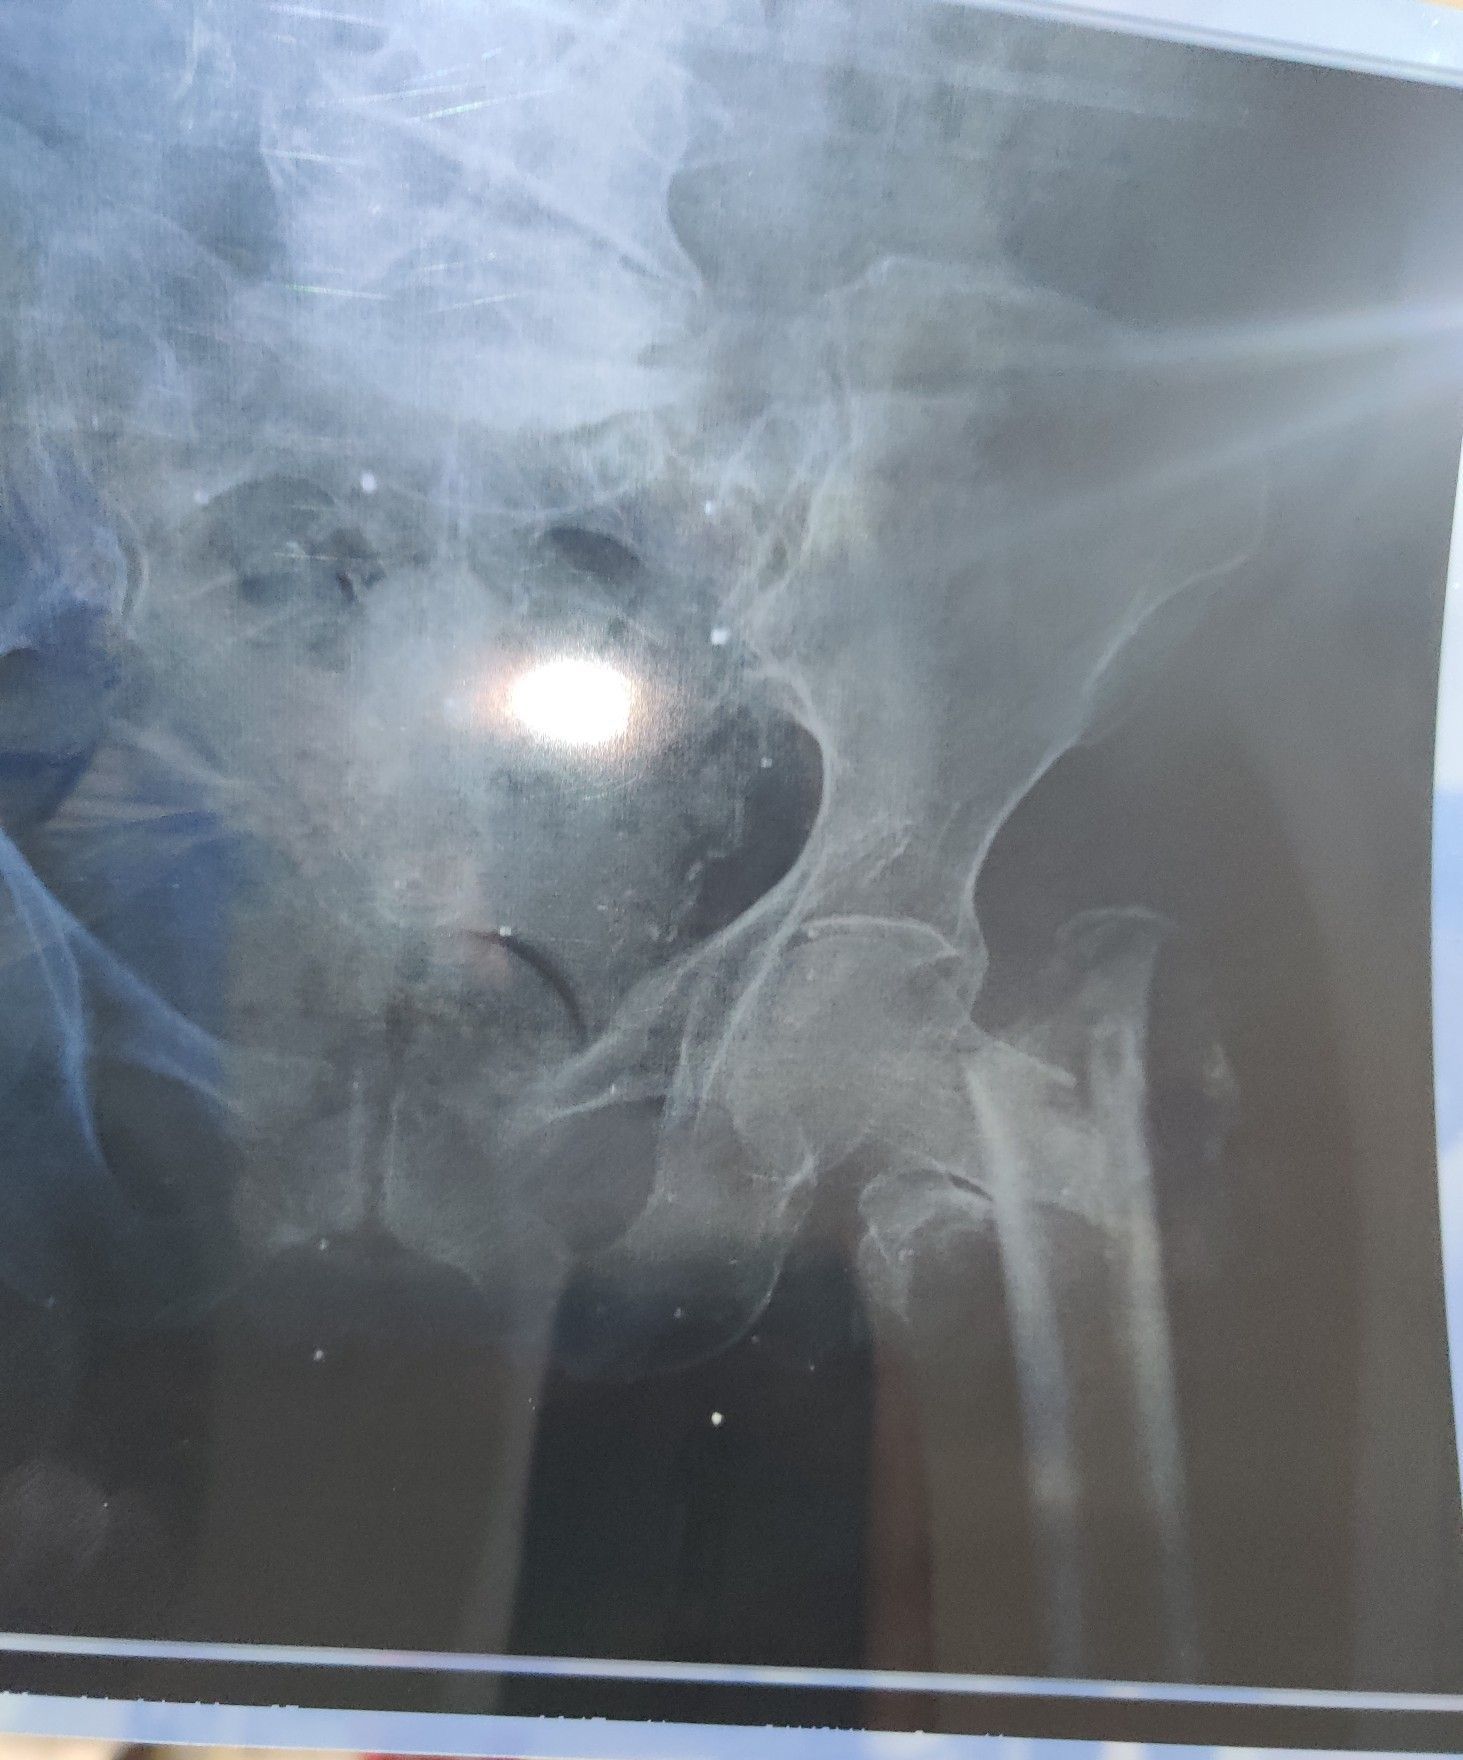

Neck of Femur Fracture

Ortho

Femur

Rta